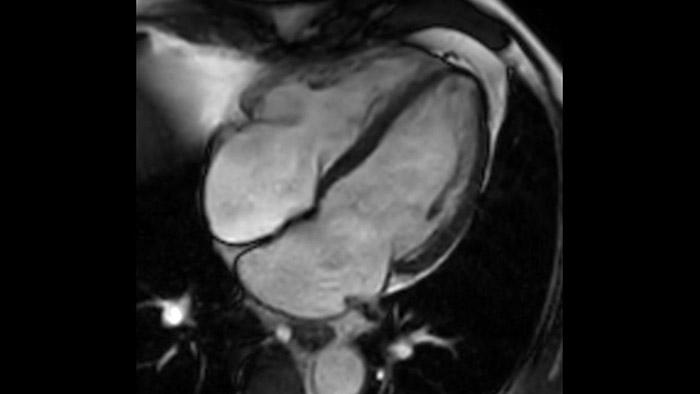

IntelliSpace Portal offers a Comprehensive Cardiac MRI Suite, providing dedicated workflows for functional analysis, viability, LGE, cardiac mapping assessment and RV/LV functional analysis in less than 5 min. per case1.

Diagnostic and prognostic utility of cardiac MR is increasing. Assess the anatomy and function of the heart using cine acquisitions, acquire information about perfusion and viability of the cardiac tissue, visualise potential edema with black blood sequence, access and even quantify tissue characterisation with CardiacQuant.